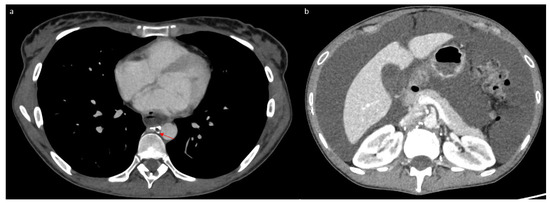

2. Case Report